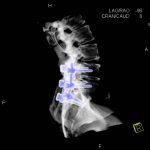

- Diagnosticul fracturilor:

-

- Unice

- Multiple

- Cu înfundare

- Complexe cranio-sinusale

- Complexe cranio-etmoidale

- Complexe cranio-orbitare

- Complexe cranio-faciale